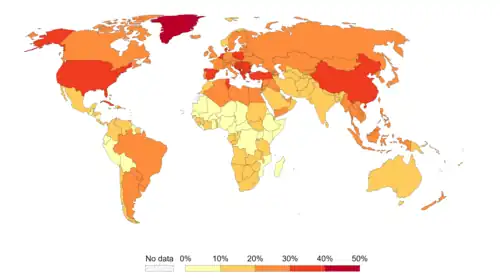

Worldwide, approximately 18% of cancer cases are related to infectious diseases.[9][73] This proportion varies in different regions of the world from a high of 25% in Africa to less than 10% in the developed world.[9] Viruses are the usual infectious agents that cause cancer but bacteria and parasites also contribute. Infectious organisms that increase the risk of cancer are frequently a source of DNA damage or genomic instability.